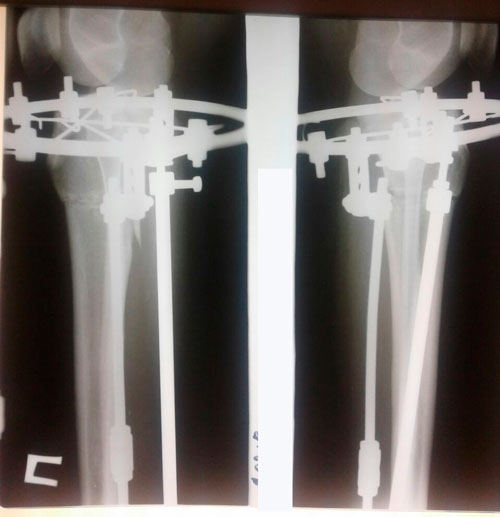

Дата операции 17.01.2018г.

Дата снятия аппаратов 21.05.2018г.

Срок лечения 123 дня.